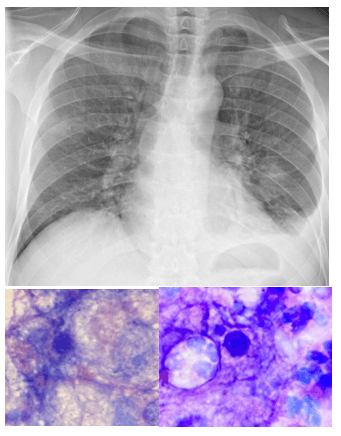

A 35 year old male presented to the emergency department with left-sided chest pain, a new cough and pain that gets worse with inspiration. The past medical history was significant for HIV, recurrent syphilis, rectal high-grade dysplasia, proctitis with possible rectal abscess with concomitant Herpes Simplex Viral infection and Cytomegalovirus colitis. This patient was not compliant with antiretroviral therapy (ART) and his CD4 count was <100 at admission. In the ED, a chest X-ray was performed which revealed bilateral patchy, peripheral mass-like opacities with ground glass halos (Figure 1). Routine respiratory cultures of sputum and bronchoalveolar lavage (BAL) revealed no significant observations; mainly respiratory flora was reported. However, hematology staining of BAL revealed multiple fungal elements consistent with Pneumocystis jirovecii organisms (Figure 2).

Induced sputum, bronchoalveolar lavage fluid, or lung tissue are the commonly accepted specimens received in clinical laboratories for direct diagnosis of P. jirovecii. Microscopically, the life cycle of Pneumocystis consists of at least two different life cycle forms of Pneumocystis organisms: the trophic form and the cyst form. The trophic form generally measures ∼2 µm in greatest diameter and in contrast, the cyst is significantly larger, measuring ∼8–10 µm in greatest diameter. The rigid Pneumocystis cyst wall is formed of β-glucan, which warrants detection of systemic Pneumocystis infections using Fungitell testing.4 Trophic and cyst forms can be detected with Papanicolaou, Gram-Weigert, or Wright Giemsa, Gomori methenamine silver (GMS), or calcofluor white. The sensitivity of the interpretation of these stains depends upon the expertise of the observed to differentiate Pneumocystis from artifacts and other fungi such asand Histoplasma capsulatum. The use of monoclonal antibodies with Immunofluorescent antibody stains directed against human Pneumocystis epitopes, can enhance direct detection of this organism in clinical specimens.5